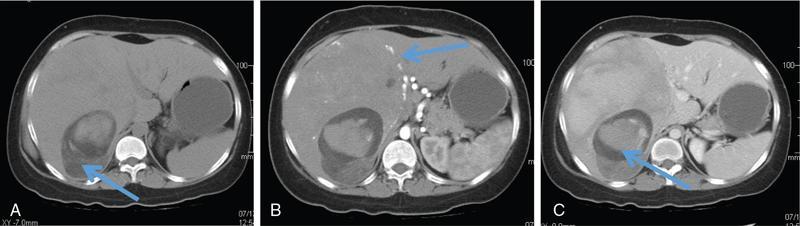

Excessive triglyceride accumulation within hepatocytes is defined as hepatic steatosis. Major conditions associated with hepatic steatosis include alcoholic fatty liver disease (AFLD) and nonalcoholic fatty liver disease (NAFLD). Causes of hepatic steatosis are discussed in Table 9.10.3. NAFLD is the most common form of hepatic steatosis and discussed in detail below. Up to 90% of patients with chronic alcoholic intake have fatty liver. Those with pure AFLD have a 10% risk of progressing to cirrhosis. Consumption of 30 g ethanol/day shows increased risk of chronic liver disease and cirrhosis. Other risk factors include female sex, obesity, cigarette smoking, obesity and associated risk factors. These factors are divided into 2 main categories which can cause fatty liver: inborn errors of metabolism and acquired metabolic disorders. Inborn errors of metabolism include abetalipoproteinemia, galactosemia, glycogen storage disease, hereditary fructose intolerance, homocystinuria and Wilson disease. Inflammatory bowel disease, jejunoileal bypass, malnutrition, starvation and total parenteral nutrition are acquired metabolic factors associated with increased risk. Chronic HCV infection, is associated with hepatic steatosis, with prevalence of 40%–80%. Hepatic steatosis can be seen as an adverse reaction to some medications such as tetracycline, valproic acid, some of chemotherapeutic agents, dexamethasone, amiodarone, methotrexate, tamoxifen and acetylsalicylic acid. Either microvesicular or macrovesicular steatosis can be observed in drug-induced hepatic steatosis. It generally occurs with therapy lasting several weeks or months and is reversible after discontinuation. The leading cause of hepatic steatosis in paediatric population is NAFLD. Six per cent of these patients develop cirrhosis and end-stage disease. Other less common causes include starvation and malnutrition, drugs (glucocorticoids, oestrogens, tetracyclines, and methotrexate), intoxications (carbon tetrachloride, organic phosphates, organic solvents, and alcohol), metabolic disorders, hepatitis C infection, and total parenteral nutrition. NAFLD is defined as steatosis affecting >5% of hepatocytes in the absence of a secondary cause. NAFLD represents a spectrum of disease, ranging from simple steatosis to steatohepatitis through to fibrosis and cirrhosis and in some cases hepatocellular carcinoma. NAFLD is a growing epidemic worldwide in part due to obesity and insulin resistance leading to liver accumulation of triglycerides and free fatty acids. Nonalcoholic steatohepatitis (NASH) is defined by histologic terms as a necroinflammatory process whereby the liver cells become injured in a background of steatosis. 20% of patients with NAFL progress to NASH, which progresses to fibrosis and cirrhosis over a 15-year time period (Fig. 9.10.3). The definition of NAFLD requires imaging or histology evidence of steatosis and no causes for secondary hepatic fat accumulation like significant alcohol intake, drugs or hereditary disorders (Table 9.10.4). The incidence of NAFLD ranges from 20% to 30% in Western countries and 5%–18% in Asia. As it currently stands, NAFLD represents the second most common reason to be listed for a liver transplant. The prevalence of NAFLD is higher in patients with obesity, diabetes, and patients with hyperlipidaemia. Prevalence increase with age from less than 20% at age 20 to more than 40% over 60 years of age. Males show a higher risk for progression to NASH and fibrosis (Table 9.10.5). Up to 90% of patients with NAFLD have simple steatosis, and about 30% of patients with NAFL develop NASH, and in again about 30%–40% of NASH patients the disease progresses to manifest fibrosis and cirrhosis NAFLD related cirrhosis has a 10-year mortality of 25% and a 5% chance of developing end-stage liver disease and HCC. The theory implicated in the pathogenesis of NAFLD is the two-hit theory. Insulin resistance, enhanced dietary influx and increased hepatic lipogenesis leading to accumulation of triglycerides (TG) and FFA in the hepatocytes is the first hit. The lipid peroxidation, mitochondrial dysfunction and inflammation resulting in hepatocyte damage and development of liver fibrosis is the second hit. The stages of NAFLD on histology range from steatosis initially to hepatic fibrosis in late stages. In the steatotic stage large (macro-) and small (micro-) vesicles of fat, predominately triglycerides, accumulate within hepatocytes. The affected parenchyma is divided into thirds: 5%–33%, 34%–66% and >66% and graded as mild, moderate and respectively. Ballooned hepatocytes with accompanied steatosis and inflammation are characteristic of the steatohepatitis stage. Fibrosis has a characteristic appearance with early lesions showing a perisinusoidal deposition followed by periportal fibrosis which progresses to bridging. Raised GGT is the most common liver enzyme elevated in NAFLD. Transaminases are within normal range in 80% patients. No specific blood tests can diagnose NAFLD. Liver biopsy has remained the gold standard for diagnosis and quantification of liver fat. Drawbacks, however, include invasive nature, sampling error and procedure related complications like bleeding. Various imaging techniques are currently available in diagnosing and quantifying liver fat. MRI in particular proton density imaging and MR Spectroscopy have revolutionized imaging of fatty liver. Normal liver parenchyma is the same as or slightly more echogenic than the adjacent kidney and spleen. Fat deposition leads to increased echogenicity of liver. Decreased beam attenuation in patients with fatty change leads to poor visualization of structures such as intrahepatic vessels, bile ducts and liver lesions and in severe cases diaphragm (Table 9.10.6). Fatty liver can be graded on USG as: US has a fair accuracy of detecting the moderate to severe hepatic steatosis with sensitivity of about 90% and specificity of about 95% for patients without concomitant chronic liver disease. Ultrasound is observer and equipment dependent. Confounding factors such as large body hiatus may lead to overestimation of hepatic steatosis due to beam attenuation by overlying fat. Conditions like fibrosis, inflammation can affect interpretation. The ratio between the mean brightness level of liver and right kidney is called the Hepatorenal sonographic index. A cut off of 1.49 has a high sensitivity and specificity for diagnosis of steatosis >5%. The main advantages of CT for assessing steatosis are relatively fast acquisition, ease of performance, and quantitative results. Estimation of fatty liver is done on non-contrast enhanced images. The normal liver density is around 60 HU, which is approximately 10 HU higher than normal spleen. Fat accumulation in the liver manifests as proportionate decrease in density. Both the absolute and relative (to the spleen) values are used to characterize steatosis; a cut-off value of 40 HU has been suggested to predict fat content greater than 30% (Figs. 9.10.6 and 9.10.7) Attenuation difference between liver and spleen on unenhanced CT scan is a commonly used quantitative parameter to evaluate hepatic steatosis. This avoids errors in attenuation value measurement from different CT scanners and different reconstruction algorithms. Normal liver parenchymal attenuation on nonenhanced CT is slightly higher than the spleen. Liver attenuation progressively decreases as percentage steatosis increases (Table 9.10.7) (Fig. 9.10.8) Methods of liver fat quantification on CT have been discussed in details in chapter on liver transplant. Limited diagnostic accuracy for detecting mild degree hepatic steatosis is one of major drawback of CT. Disorders causing hyperdensity of liver such as iron, glycogen deposition can lead to errors in interpretation. The concomitant presence of iron and fat may not be accurately diagnosed on CT. Low CT density values may also be caused by oedema and inflammation. Likewise, the spleen is an imperfect reference standard as it can be affected by haemosiderosis and haemochromatosis in a small minority of patients. Dual-energy CT with its ability to perform material decomposition is more accurate in quantifying hepatic steatosis and allows staging of fibrosis. Imaging is done with two different energies (typically 80 kVp and 140 kVp). DECT has the potential to quantitate liver fat content independent of ROI (region of interest) placement. Magnetic resonance imaging (MRI) is presently the most accurate imaging modality for the evaluation of hepatic steatosis. Several different methods have been developed and introduced in MRI for the evaluation of hepatic steatosis. In this technique typically, two gradient echoes are acquired, one employing a TE in which the water peak (4.7 ppm) and the dominant fat peak (1.3 ppm) are ‘out of phase’ and hence subtractive (SOP), and the other using a TE in which the two peaks are ‘in phase’ and therefore additive (SIP). Because two echoes are acquired, this is often called ‘dual-phase’ or ‘dual echo’ imaging. Fat Signal Percentage is calculated as [SIP – SOP]/[2 × SIP] ×100. The dynamic range of magnitude based chemical shift techniques has typically a 0%–50% signal fat-fraction (Fig. 9.10.9) This technique uses both magnitude and phase information from three or more images acquired at different echo times appropriate for more accurate separation of water and fat signals as against only magnitude information in dual-echo. These methods provide estimates of fat fraction with a dynamic range of 0%–100%. Proton density Fat fraction (PDFF) is calculated as Sf/(Sw + Sf) where Sw = SI of the water component, Sf = SI of the fat component. PDFF specifically reflects the concentration of triglycerides in the hepatocytes as lipids within the other structures such as cell membranes and organelles are occult. Sensitivity up to 96% and specificity up to 100% for detecting any degree of steatosis have been reported. A fat-fraction threshold of 5.56% is commonly used to define steatosis; however, the optimal cut-off value still needs to be defined (Figs. 9.10.10 and 9.10.11). MRS can directly measure the chemical composition within tissue based on the frequency composition of the signal originated from the voxel of interest. Water proton peak appears as a single peak at 4.7 ppm, whereas fat peaks appear as multiple peaks around 1.3 ppm. PDFF can be calculated as the ratio of the sum of the signal intensities derived from the protons in fat divided by the sum of the signal intensities originated from the protons in both fat and water (Fig. 9.10.12). TABLE 9.10.8 MRS data are usually obtained from a single voxel manually placed in the liver parenchyma usually right posterior segment of the liver. Reported MRS sensitivities and specificities for detection of mild hepatic steatosis are 80.0%–91.0% and 80.2%–87.0%, respectively, outperforming CT and US. MRS can also provide excellent reproducibility of measurement. It is also unaffected by confounding factors like fibrosis, iron overload and glycogen. Small sample volume usually less than 3 × 3 × 3 cm3 is a major limitation of MRS, particularly in patients with uneven fatty change. Despite these practical limitations, MRS is considered to be the gold standard MR method for hepatic fat quantification. This is the most frequently encountered pattern and considering the homogenous involvement poses no diagnostic dilemma. Focal fat deposition and focal sparing in diffuse fatty liver are less common. These usually occur in specific locations like adjacent to falciform ligament or ligamentum venosum, in portal hepatis or gallbladder fossa. Imaging findings are suggestive of fatty pseudolesions rather than true masses. Occurrence in characteristic locations, absence of mass effect on vessels and structures, geographic configuration and contrast enhancement similar to or less than adjacent liver (Fig. 9.10.13). Fat deposition around insulinoma metastasis can occur as a local effect of insulin on the liver parenchyma. On ultrasound, it appears as an echogenic rim shows signal drop on out of phase images. Eisenberg has reported perilesional steatosis around focal nodular hyperplasia. Sometimes multiple small foci and seen scattered throughout the liver. These may appear as small round nodules (Fig. 9.10.14). Opposed phased imaging is more useful than CT or US to establish diagnosis. These may, however, pose a diagnostic dilemma in patients with known malignancy. Perivascular fatty infiltration is a recently described entity, mostly seen in alcoholic patients. This pattern is characterized by halos of fat that surround the hepatic veins, the portal veins, or both hepatic and portal veins (Fig. 9.10.15). Normal vessels coursing through the lesion without attenuation in calibre suggest the diagnosis. Peritoneal dialysis with insulin in the dialysate in patients with renal failure and insulin-dependent diabetes. Exposure of subcapsular hepatocytes to a higher concentration of insulin results in fat deposition in the subcapsular regions. Some hepatic lesions such as hepatic adenoma, hepatocellular carcinoma, regenerative nodules and focal nodular hyperplasia can show intracellular steatosis (Fig. 9.10.16). These areas show signal drop on opposed phase. However, postcontrast imaging characteristics of these lesions allow differentiation from areas of focal steatosis. Perilesional sparing has been reported in haemangioma and hepatocellular carcinomas. This may mainly represent decreased portal flow due to either compressed or atrophic hepatocyte cords in expanding metastases or arterioportal perfusion abnormalities in haemangiomas. The differential diagnosis of focal fat infiltration is discussed in Table 9.10.9. Accurate history and chemical shift imaging showing signal drop help in differentiation of focal fat from metastasis. These are visible only during the arterial and portal venous phases after contrast agent administration. The morphologic appearance of fat deposition and perfusion abnormalities is similar. Perfusion abnormalities however are visible only during the arterial and portal venous phases (Fig. 9.10.17). They are not seen as an attenuation difference on nonenhanced CT. Periportal oedema, inflammation, haemorrhage and lymphatic dilatation may mimic perivascular fat. With the exception of haemorrhage all other conditions affect periportal region symmetrically (Fig. 9.10.18). Patients with haemorrhages may show other signs of injury. Chemical shift imaging is helpful in cases with diagnostic challenges.

CT

Liver attenuation index

Principle: Fat has low attenuation a proportionate decrease in density is seen with increasing fat accumulation in liver

Assessment of hepatic steatosis using CT is based on the measurement of attenuation value of liver parenchyma, expressed as Hounsfield units (HU)

Attenuation difference between liver and spleen on unenhanced CT scan has been the most commonly used

Cut-off value of attenuation difference to detect moderate to severe degree hepatic steatosis-9